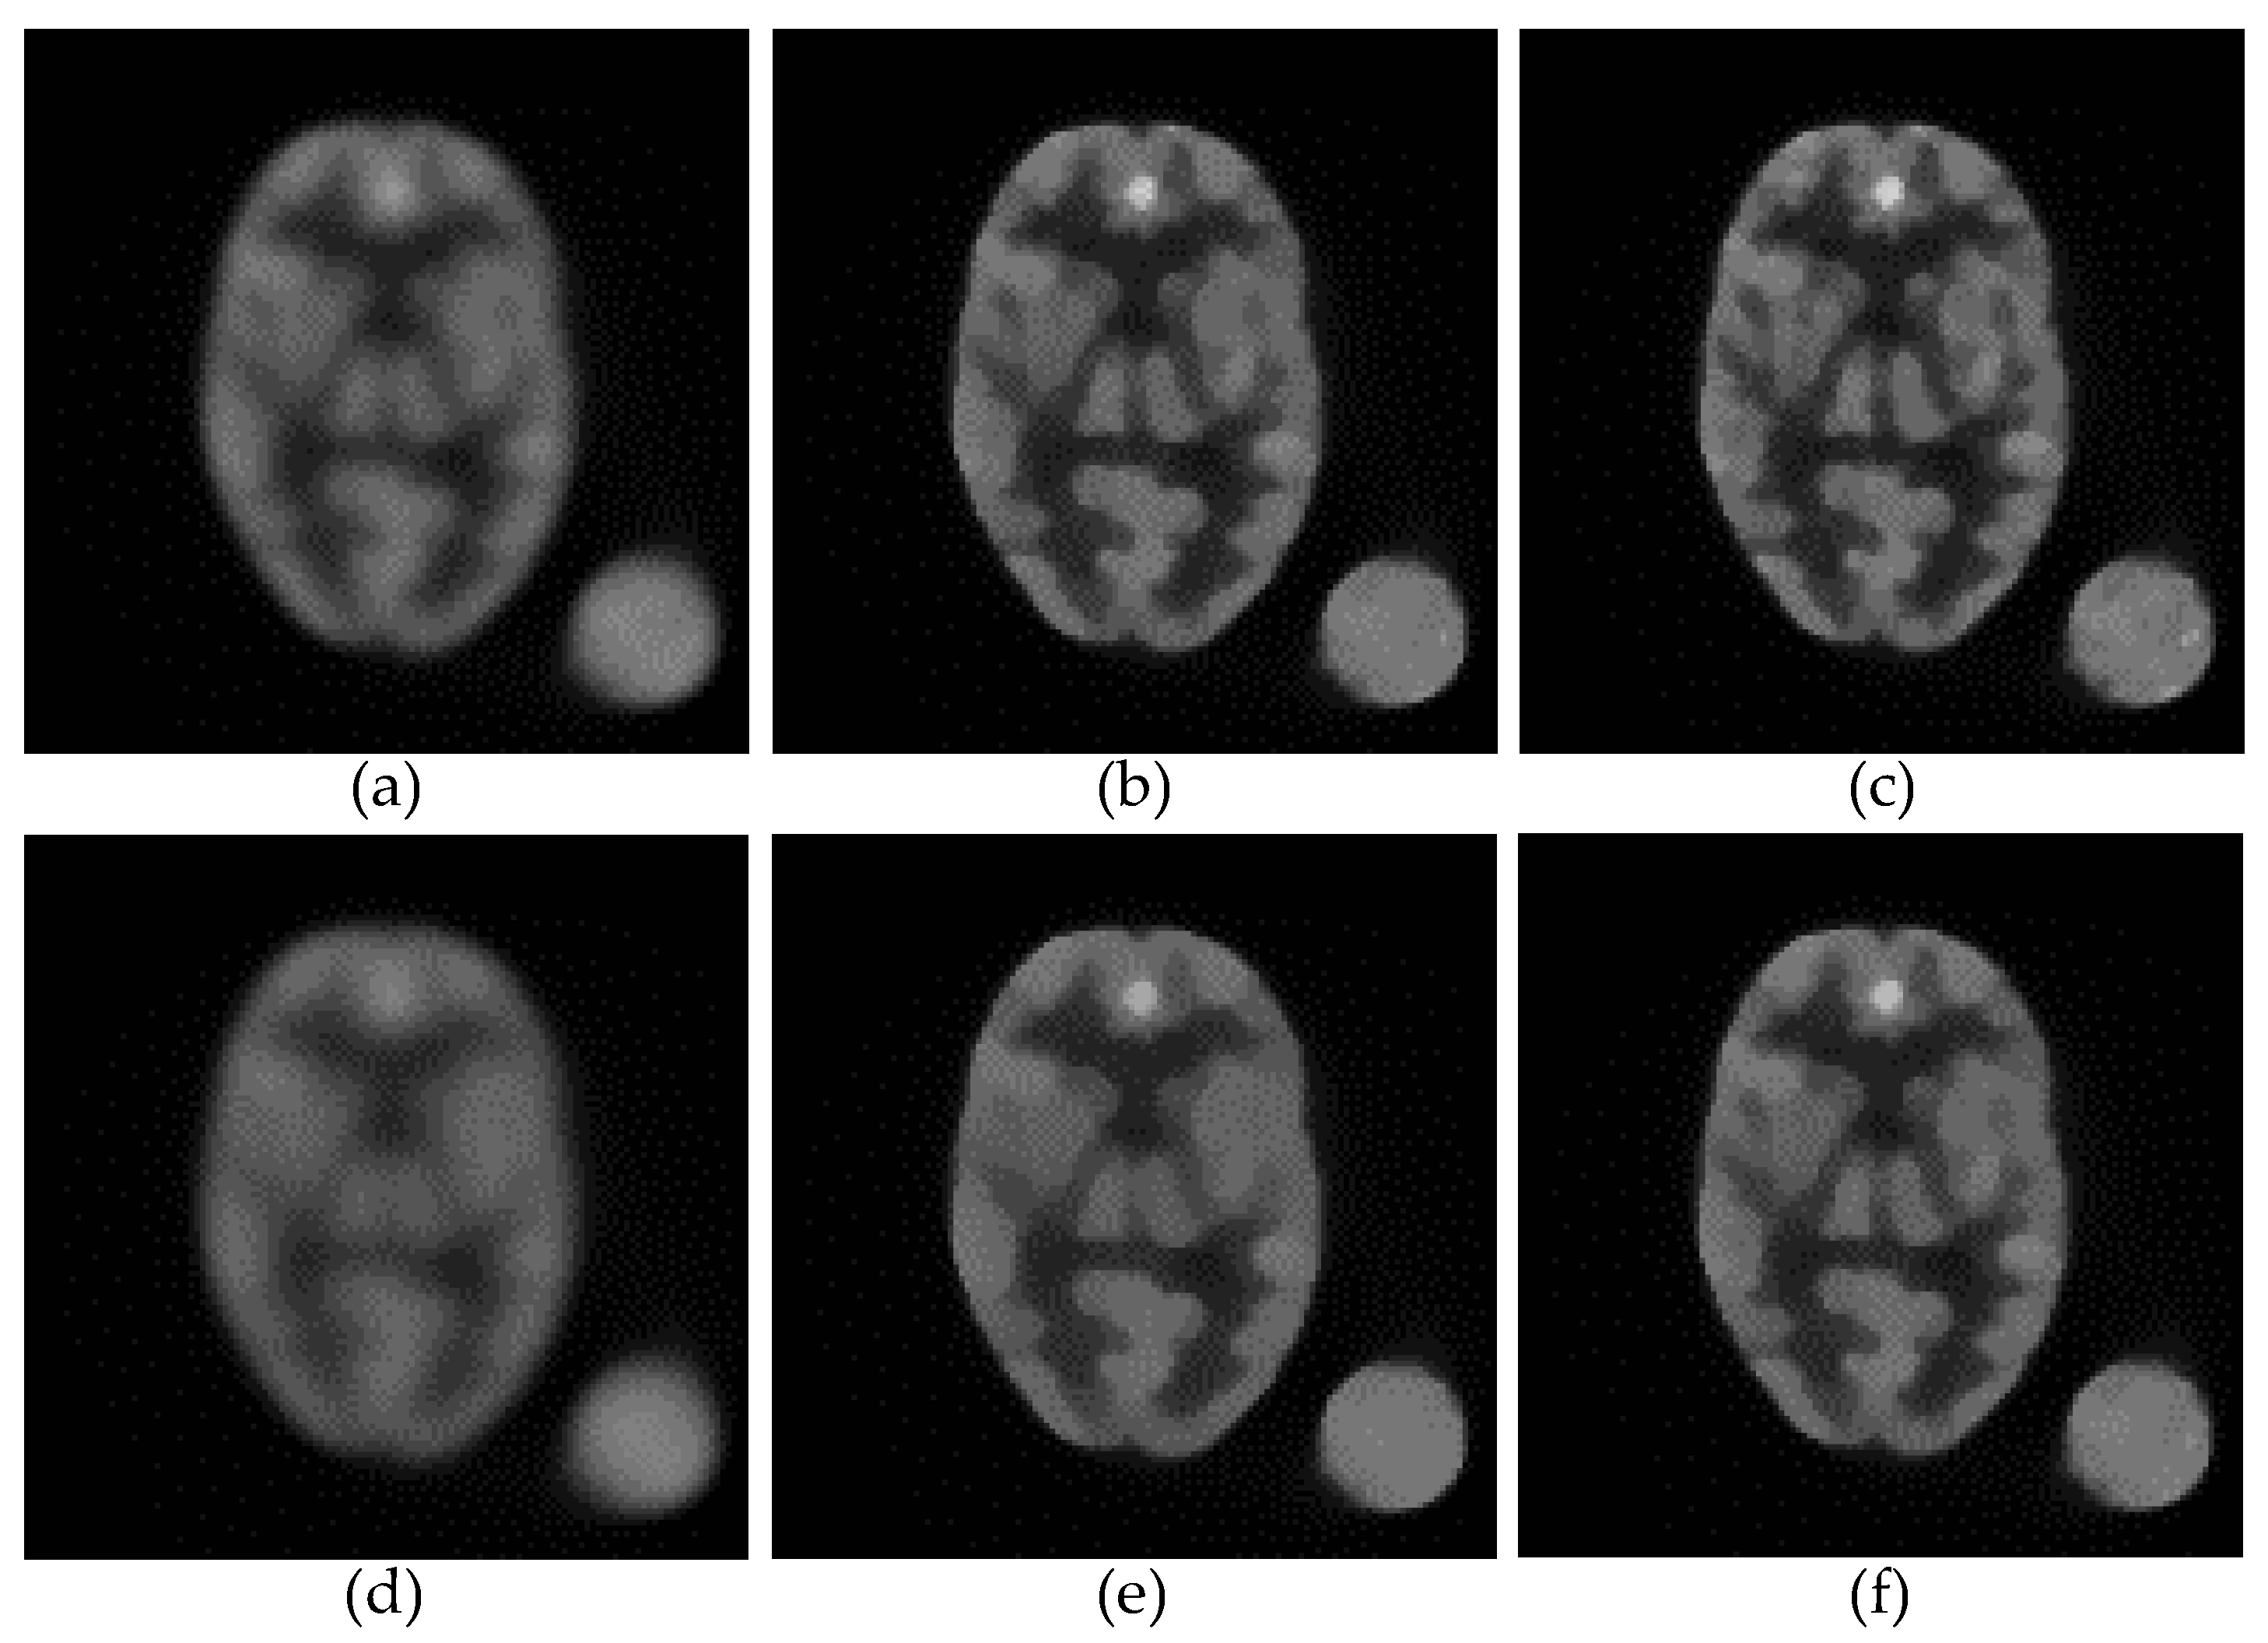

3.1. Reconstruction Accuracy